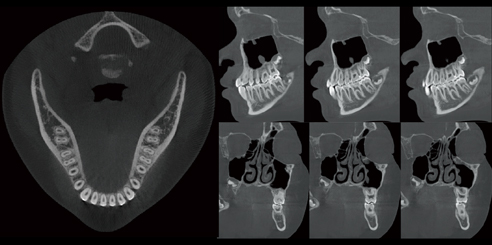

The LargeV CBCT supports CT, CEPH, and panoramic imaging in one compact system.

It delivers sharp, high-contrast images that reveal every dental structure with exceptional clarity.

Furthermore, Panoramic Images are Reconstructed from 3D Dental CBCT data for clearer visualization

Additionally, the system provides three flexible scan modes to match clinical needs. Multiple focus layers in panoramic imaging fit each patient’s dental arch perfectly.

Furthermore, AI+PAN Dental CBCT Imaging enhances precision.

- The system rebuilds panoramic views directly from CBCT data using AI.

- Panoramic auto-focus and multi-layer technology select the best curve automatically.

- Therefore, the final image is cleaner and easier to read.